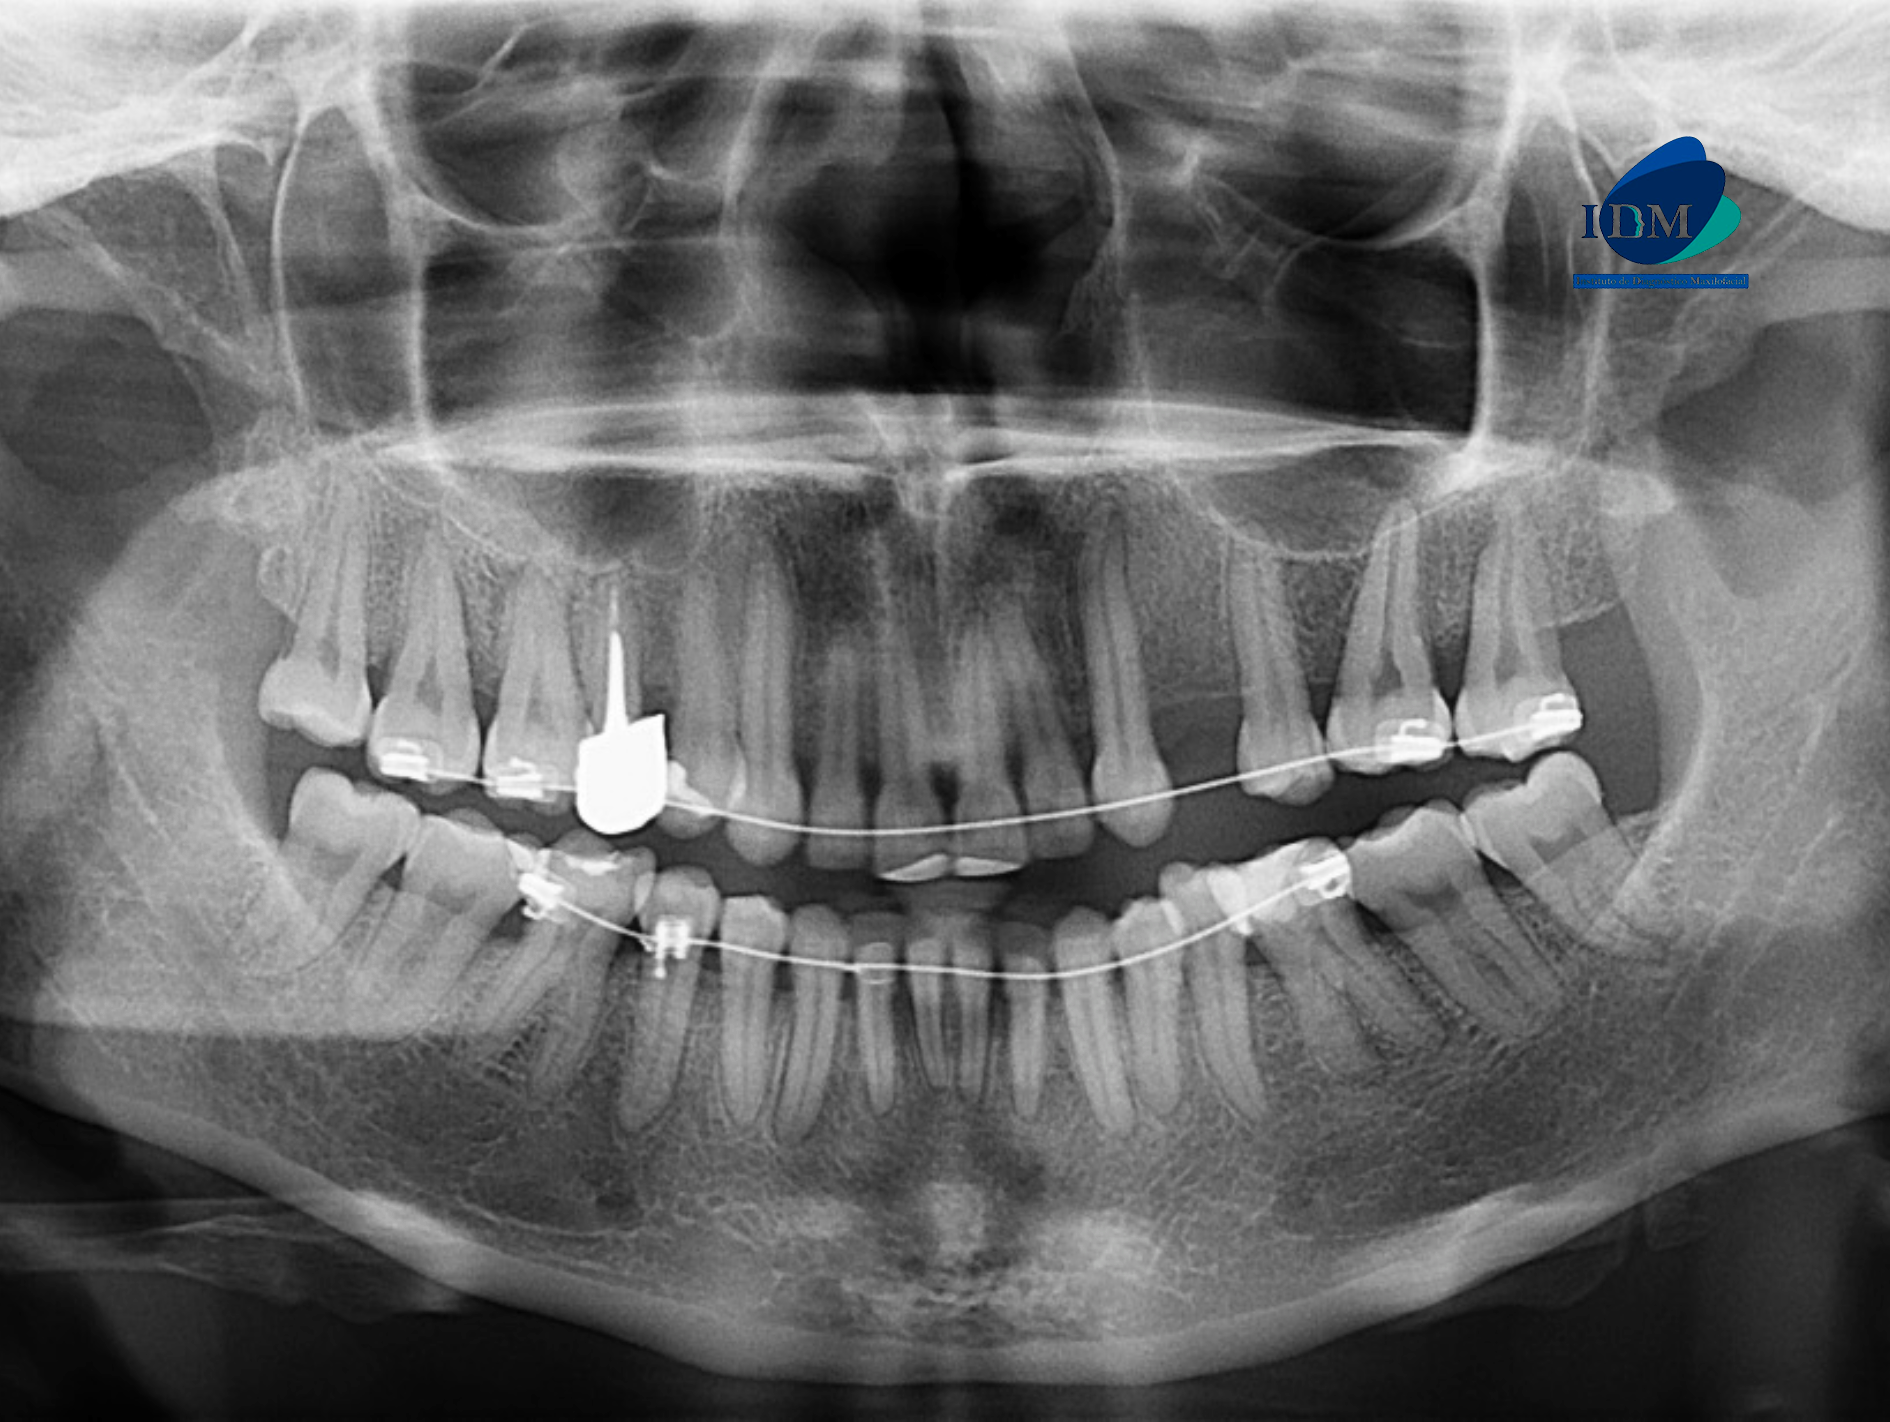

En la radiografía panorámica (Figura 1), se observa el engrosamiento de la mucosa de senos maxilares, aparatología ortodóntica en maxilar superior e inferior y múltiples restauraciones coronarias; a nivel de las piezas 37 y 47 se observa la elongación céfalo – caudal de la cámara pulpar, compatible con taurodontismo.

Radiografia Panorámica